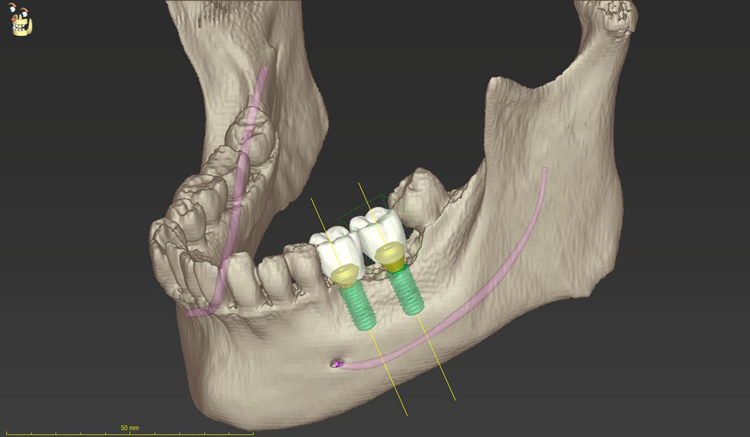

CTスキャン、痛みの少ないインプラント

インプラント治療を痛みなく安心して行うために、

信頼性の高いストローマンインプラント、専用の機材、日本国産の高性能歯科用CTスキャン、